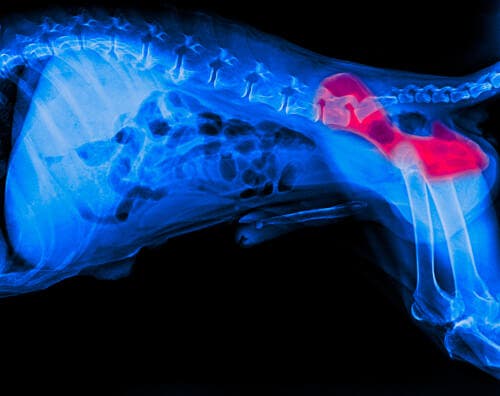

Risque accru de dysplasie de la hanche

Comme mentionné ci-dessus, les chiens se blessent souvent le dos lorsqu’ils glissent sur un sol stratifié. Il est évident que ce type de blessure nécessitera un traitement et une thérapie spécialisés pour guérir.

Les races sujettes à la dysplasie de la hanche, comme les bergers allemands, peuvent augmenter leur risque ou aggraver leur état en marchant sur un sol glissant.